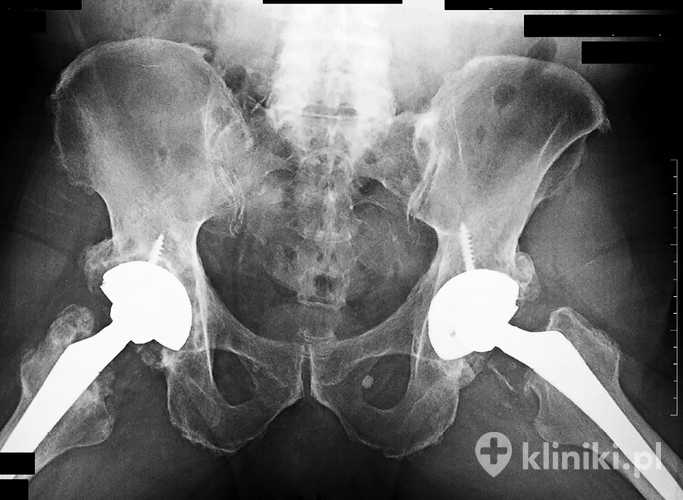

Endoproteza stawu biodrowego zastępuje uszkodzone elementy stawu, przejmując ich funkcję ruchową

Pierwszych próbnych zabiegów rekonstrukcyjnych w obrębie stawu biodrowego dokonano już w 1891 roku w Niemczech. Początkowo stosowano protezy jednoelementowe, jednak w 1953 r. chirurg angielskiego pochodzenia George McKee opracował metalowy zestaw dwuczęściowy. Przez kolejne lata wprowadzano zmiany w obrębie stosowanego metalu oraz pokryć zewnętrznych części implantów. Pojawiały się też coraz bardziej złożone konstrukcje, składające się nawet z czterech elementów.

Jak zbudowana jest endoproteza biodra i jak spełnia swoją funkcję?

Staw biodrowy tworzą głowa kości udowej oraz panewka, będąca częścią kości miednicznej. Należy do stawów kulistych; pod względem zakresu ruchomości zajmuje drugie miejsce, zaraz po stawie barkowym. Możliwe ruchy to zginanie/prostowanie, odwodzenie/przywodzenie oraz rotacje zewnętrzna i wewnętrzna.

Implantowane struktury muszą być w związku z tym precyzyjnie skonstruowane, tak by jak najbardziej odwzorowywać zakres naturalnych ruchów w stawie.

Głowa endoprotezy

Przed umieszczeniem implantowanych struktur konieczne jest przygotowanie miejsca dla nich w obrębie kości. Zdeformowana głowa jest usuwana z kości udowej, co pozwala na umieszczenie trzonu protezy w jej obrębie.

Stosuje się dwie techniki:

• pierwszą z użyciem cementu, umieszczanego w jamie szpikowej i mocującego tę część protezy;

• druga z kolei (tzw. press-fit) pomija zastosowanie łącznika, a mocowanie odbywa się bezpośrednio w obrębie tkanki kostnej.

Wybór sposobu zależy od wieku chorego i stanu jego kośćca. Kolejnym krokiem jest niejako powrót do pierwotnego wyglądu tej części stawu – na trzonie umieszczana jest metalowa część o zaokrąglonym kształcie, która odpowiada głowie wymienionej kości. W przypadku częściowej alloplastyki wystarcza tylko opisana procedura. Jeżeli konieczna jest rekonstrukcja całości stawu, potrzebne jest dalsze postępowanie.

Panewka protezy biodra

Podobnie dzieje się w obrębie panewki – nieprawidłowe struktury zostają usunięte i zastąpione implantem pełniącym rolę nasadki dla wcześniej opisanych części. Pomiędzy nimi umieszczany jest plastikowy, metalowy lub ceramiczny separator. Jego funkcją jest zapewnienie odpowiednich warunków poślizgowych między wszystkimi częściami protezy i redukcja tarcia pomiędzy nimi.